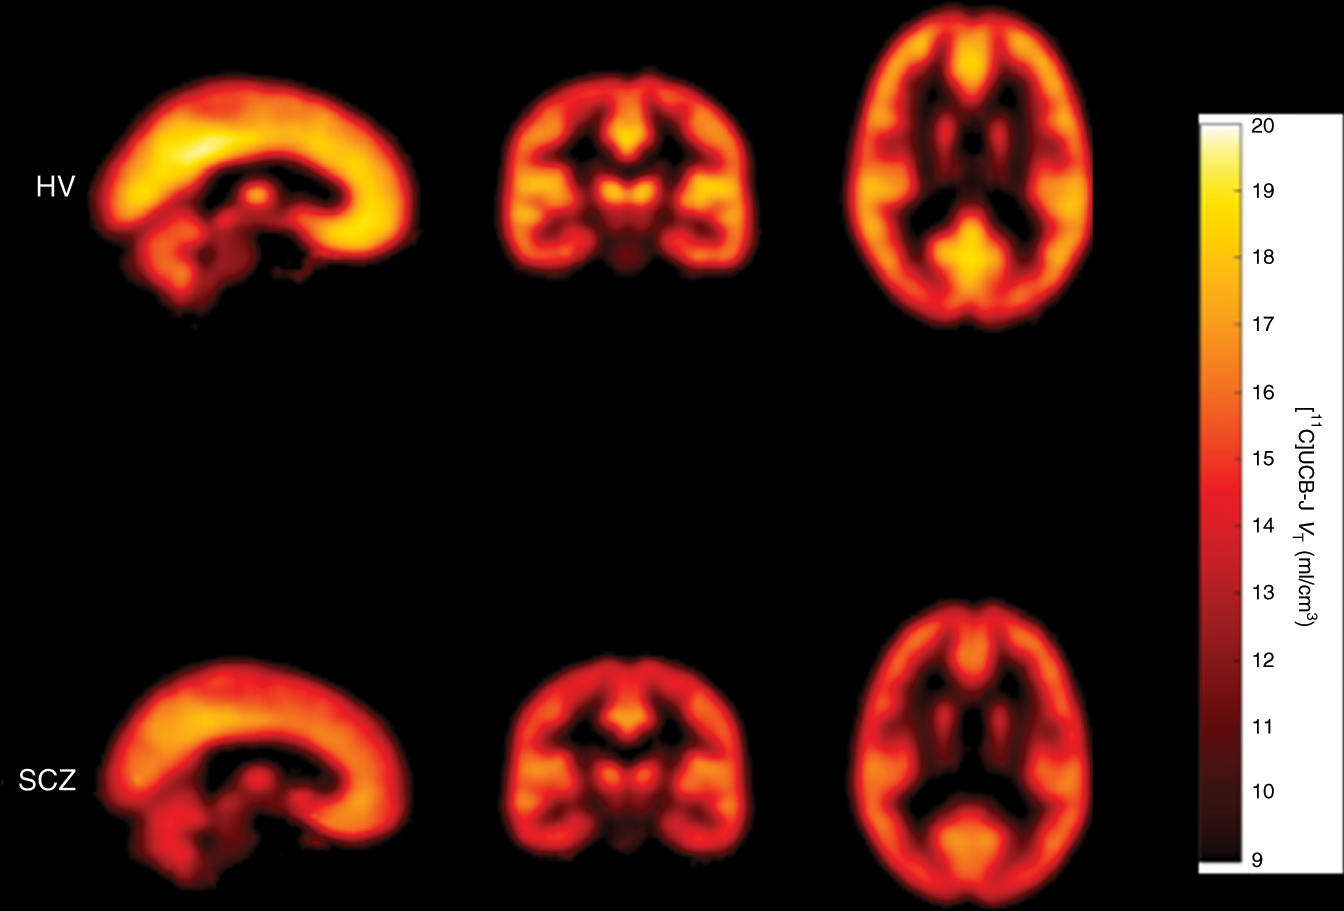

Fig. 2: Mean parametric [11C]UCB-J VT images from healthy volunteer (HV) and schizophrenia (SCZ) groups. | Nature Communications